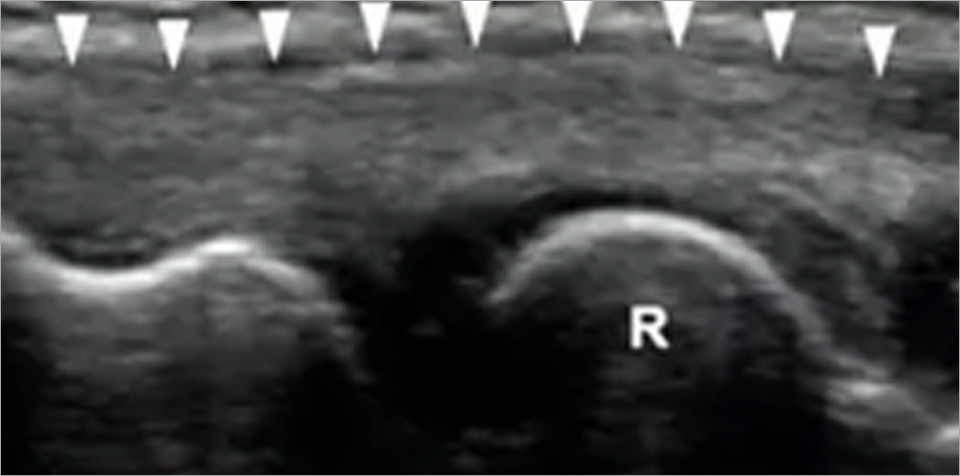

• 영상의학 검사 : 초음파

고해상도 캐논 초음파

수부전용 프로브 및 도플러를 활용

Grade 4. Tendon Tear (건 파열)

부분 또는 완전 파열이 초음파로 확인됨.